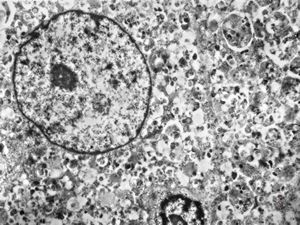

normal seromucinous salivary gland